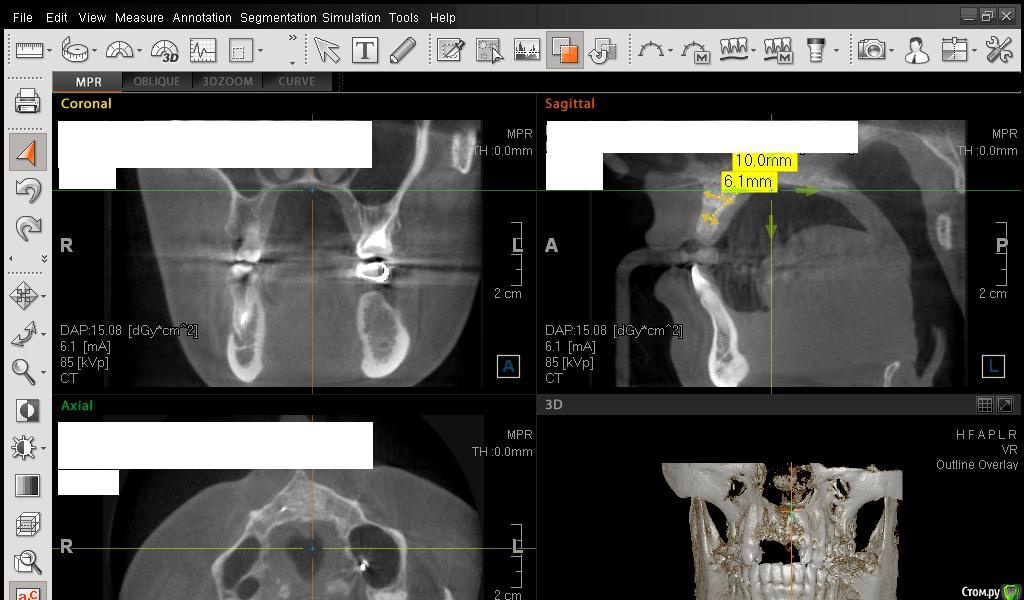

Сестричка Опубликовано 2 марта, 2015 Автор Поделиться Опубликовано 2 марта, 2015 Кажется поняла, проекция креста неправильная была? навела на область десны Ссылка на комментарий

Сестричка Опубликовано 2 марта, 2015 Автор Поделиться Опубликовано 2 марта, 2015 Еще пара срезов Ссылка на комментарий

SDC Опубликовано 2 марта, 2015 Поделиться Опубликовано 2 марта, 2015 Интересны размеры беззубого альвеолярного отростка на самой вершине его или рядом с вершиной на расстоянии 1 мм. от нее в проекции будущего местоположения имплантатов.Желательно размеры проводить рядом с объектом (как в черчении)По-моему, диаметр 3 мм. подходит для имплантации без костной пластики, но без трансплантации десны, одномоментно с имплантацией, не обойтись. 1 Ссылка на комментарий

АнтонТЛТ Опубликовано 2 марта, 2015 Поделиться Опубликовано 2 марта, 2015 Сам крест еще нужно повернуть, чтобы было одна полоса креста была параллельна краю челюсти Ссылка на комментарий